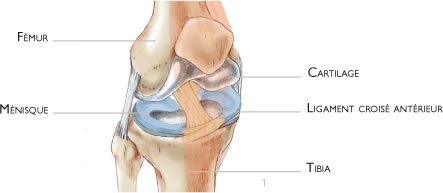

Le genou correspond à l’articulation entre la partie basse du fémur et la partie haute du tibia. Les surfaces articulaires sont recouvertes de cartilage. Les ménisques sont de petits coussins en forme de croissant qui améliorent le contact et jouent le rôle d’amortisseurs entre le fémur et le tibia (figure 1).

La stabilité du genou est assurée par des ligaments qui sont des sortes de rubans plus ou moins élastiques. Le ligament croisé antérieur, situé à l’intérieur de l’articulation, relie la partie antérieure du tibia à la partie postérieure du fémur. Il empêche le tibia de partir en avant et stabilise le genou lors des mouvements en rotation (figures 1 et 5).